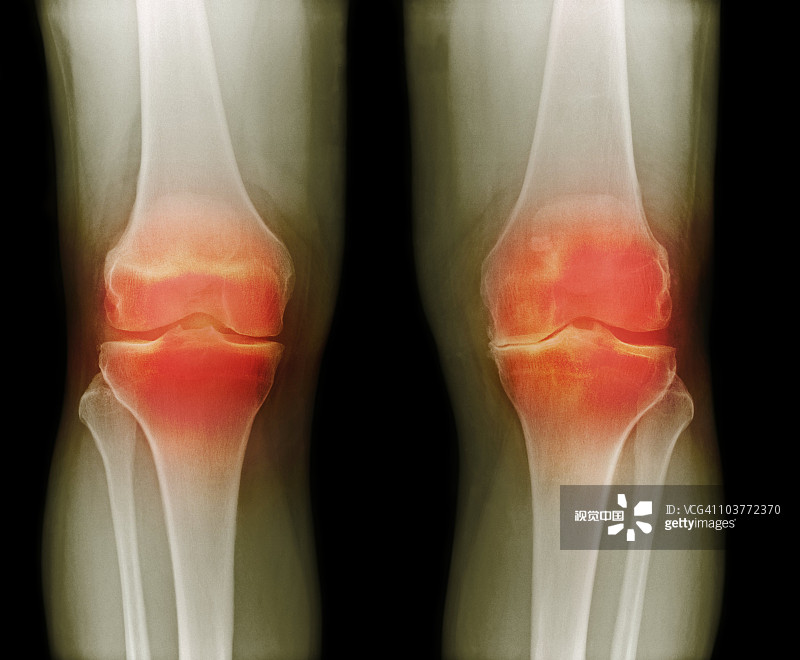

適應癥:膝骨關(guān)節炎

貴醫附院 | 人臍帶間充質(zhì)干細胞治療膝骨關(guān)節炎患者的1期臨床試驗